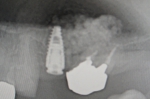

サイナスリフト(骨移植)併用インプラント埋入

ご覧の通り全く骨がないので骨を造りインプラントを埋入しました。

隣の歯も状態が良くなく予後が悪そうです。

抜歯後はインプラントをご希望でしたので、サービスで同部にも骨を移植しておきました。

これで次回オペ時の患者さんの移植のリスクが軽減しました。